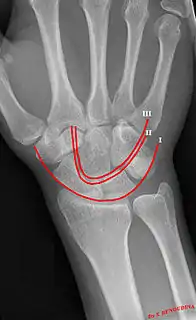

Gilula carpal arcs.

Gilula's lines are three arcs drawn on an AP radiograph of the wrist used to assess the alignment of the carpal bones.[1]

There should be no step-off in the contour of the lines when drawn on a normal wrist.

| First arc | running along the proximal convexity of the scaphoid, lunate and triquetrum |

| Second arc | running along the distal concavities of the scaphoid, lunate and triquetrum |

| Third arc | running along the proximal curvatures of the capitate and hamate |